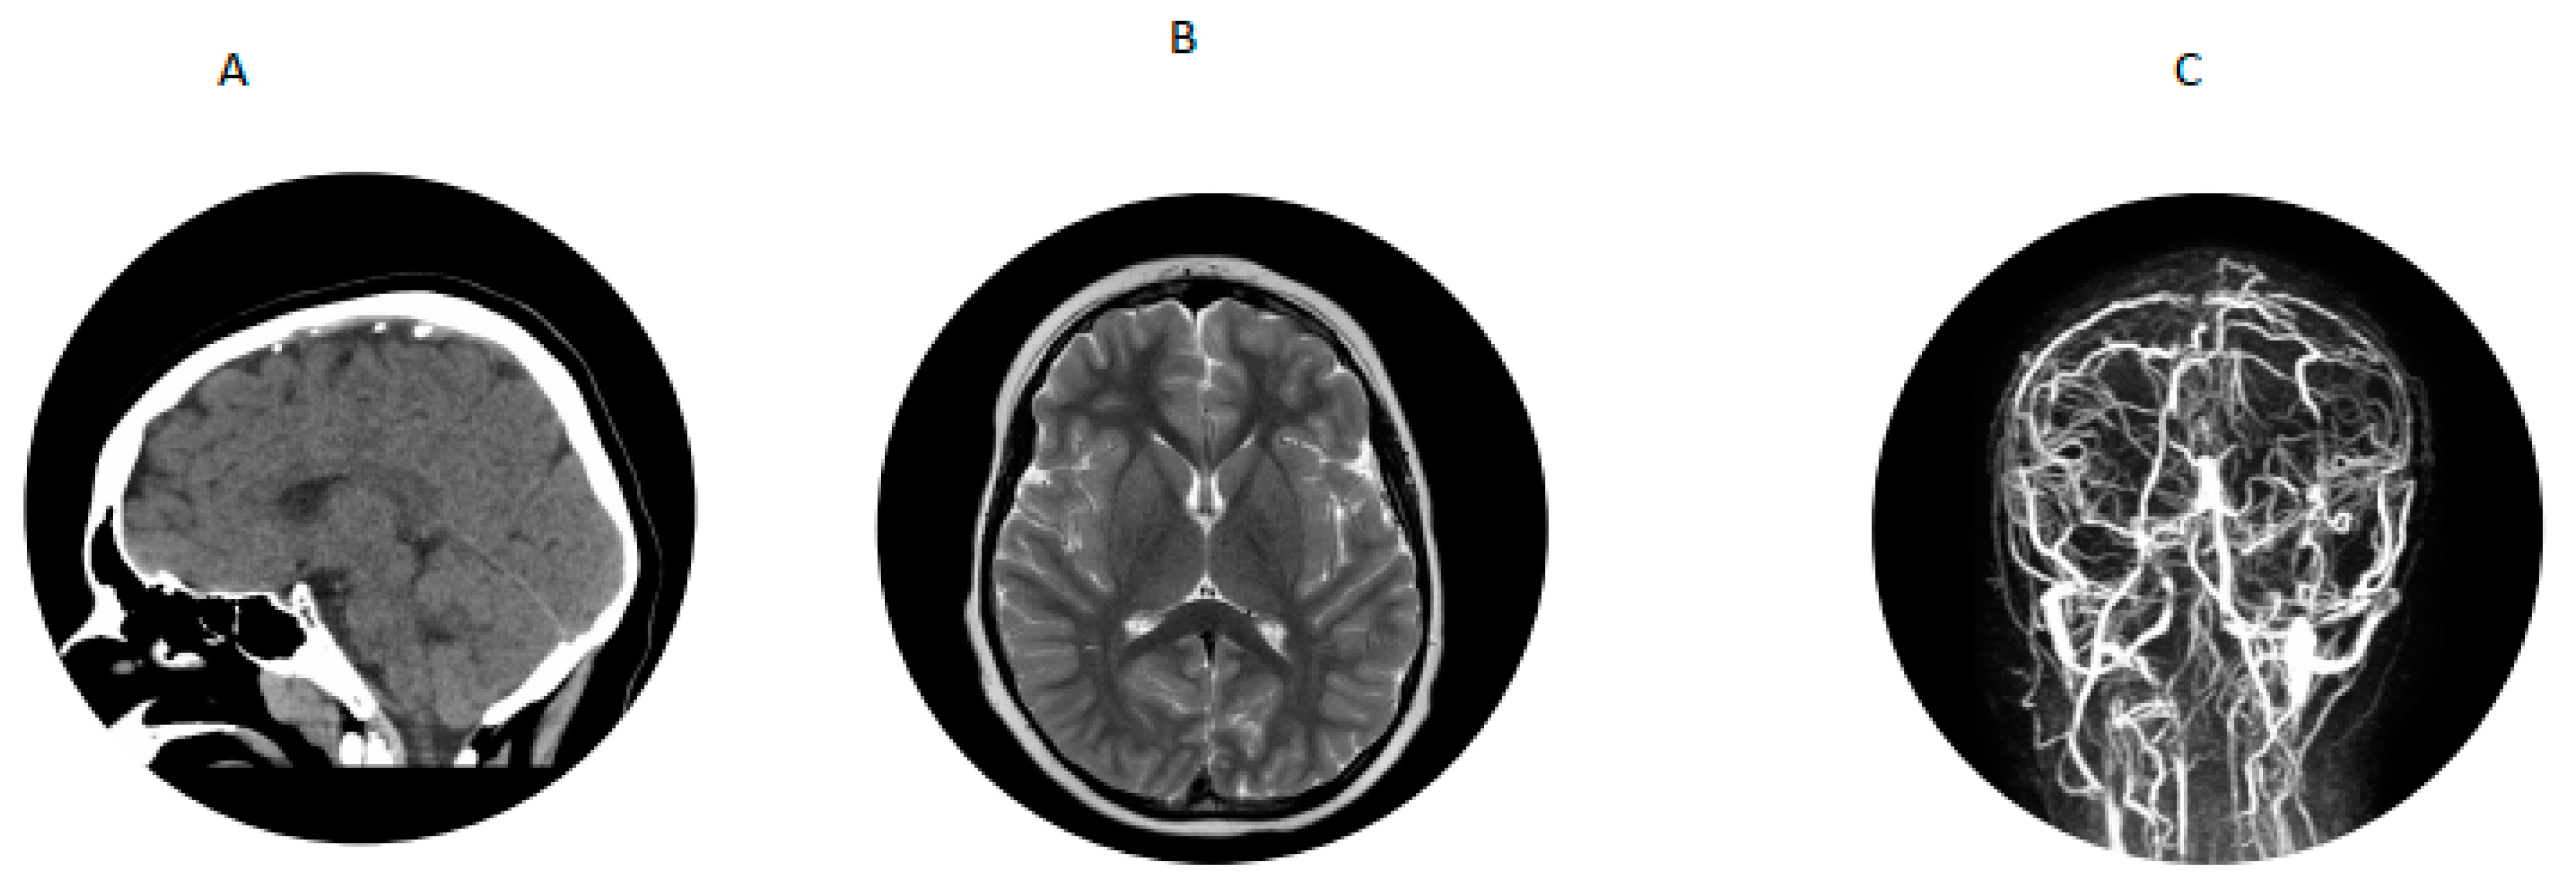

A 7-year-old boy with history of hypertension, familial tall stature and generalized overgrowth was admitted for persistent vomiting, mild leukocytosis of 14,700 and mycoplasma pneumonia. Initial brain MRI was reported as normal. He developed generalized tonic clonic seizures and left hemiparesis on day 3 of hospitalization. Bedside glucose and serum electrolytes were normal. Ammonia was mildly elevated at 58 µmol/L but repeat was less than 9; lipase was 1273 U/L (normal is 23–300 U/L). An emergency head CT scan was read as normal. Neurology was consulted and he was transferred to the pediatric intensive care unit for closer monitoring. A video EEG in the ICU was suggestive of a right > left posterior quadrant cerebral dysfunction. Dilated funduscopic examination showed edema of the optic disc bilaterally without obscuring overlying vessels. Lumbar puncture showed an opening pressure greater than 38 cm of water (normal is less than 25 cm water) with normal cell count. He was started on acetazolamide for pseudotumor cerebri. MRV showed extensive dural venous sinus occlusive disease with extensive superficial and deep collateral veins and review of the previous brain MRI showed a filling defect in the superior sagittal sinus consistent with dural sinus thrombosis (Figure 2) and papilledema. Hypercoagulable work-up showed mildly decreased antithrombin III activity (80%; reference range was 83% to 128%). Factor V Leiden, prothrombin gene mutation, lupus anticoagulant and protein S were normal and protein C activity was low (63% with reference range of 70% to 140%). Metabolic work-up showed plasma homocysteine 71.9 (reference range was 6.6 to 14.8 µmol/L); plasma amino acids showed methionine of 448 µmol/L (reference range was 14 to 50) and free homocystine was 7 (reference range was 0–2 µmol/L). Serum methylmalonic acid was 0.15 (normal is 0.0 to 0.4 µmol/L), serum folate was 14.4 (reference range is 7 to 34.1 ng/mL), serum vitamin B12 was 244 (reference is 213 to 816 pg/mL). Blueprint Genetics Laboratory Homocystinuria Core Panel Plus showed a compound heterozygote pathogenic variant c.325T>C (p.Cys109Arg) and a variant of uncertain significance c1604C>T (p.Thr535Ile) in the CBS gene.

Figure 2.

For patient 2. (A) CT scan showing thrombosis of superior sagittal sinus. (B) Brain MRI showed filling defect in superior sagittal sinus. (C) MRV showing dural venous thrombosis with extensive superficial and deep collateral veins.